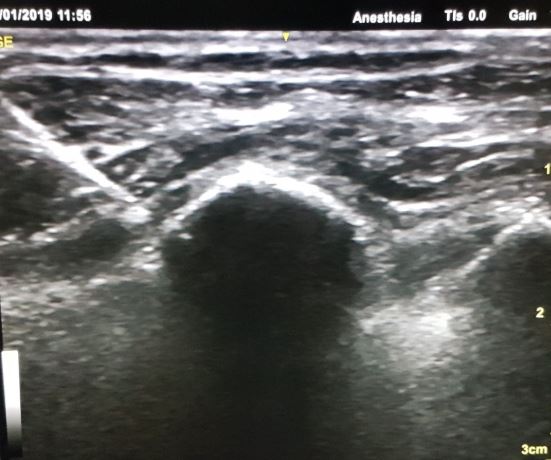

PECS 1 BLOCK: Between Pectoral major and minor. MPEC 2 BLOCK: Between pectoral minor and serratus

- The catheter was placed between pectoralis major and minor in Group PEC1 and between pectoralis minor and serratus anterior in Group mPEC2 before wound closure under direct vision by the operating surgeon.